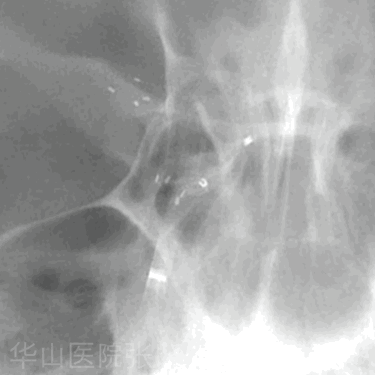

Figure 2. Working projection I was selected to show the aneurysm neck and proximal parent artery, not the daughter sac. 图 2. 工作角度 I 用于显示动脉瘤颈和近端载瘤动脉,而不是子瘤。

Figure 5 GIF. Working projection II was selected to show the risk point-daughter sac. 图 5. 工作角度 2 用于显示子瘤这一危险点。